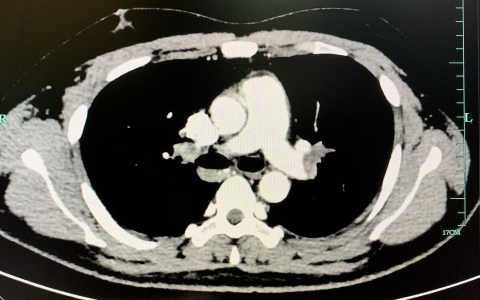

NEJM: 肺栓塞

肺栓塞是一种较常见且可致命的静脉血栓栓塞症,各科室临床工作均可能涉及。其临床表现多变,通常无特异性,诊断困难。全球肺栓塞年发病率约为1/1000人,近20%的患者在发病90天内死亡…